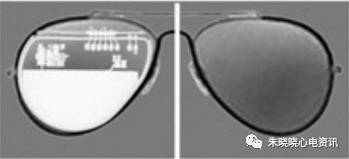

波士顿科学起搏器外形和太阳镜片类似(图4)

图4 波士顿科学起搏器